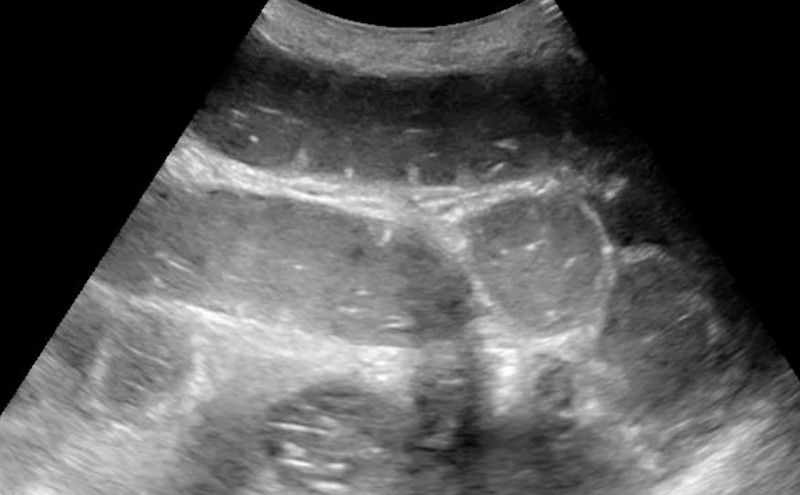

- The small bowel can be identified by visualizing the plicae circularis. Bowel wall edema in SBO can accentuate these structures, creating the “piano key sign” or “keyboard sign.” Of note, the analogous haustra of the large intestine are sparser and spaced much further apart.

Video 4a. Jejunal keyboarding in a patient with a SBO

Video 4b. SBO with “piano key sign” - Free fluid interposed between loops of bowel suggests higher grade SBO and makes the need for surgical intervention more likely.13